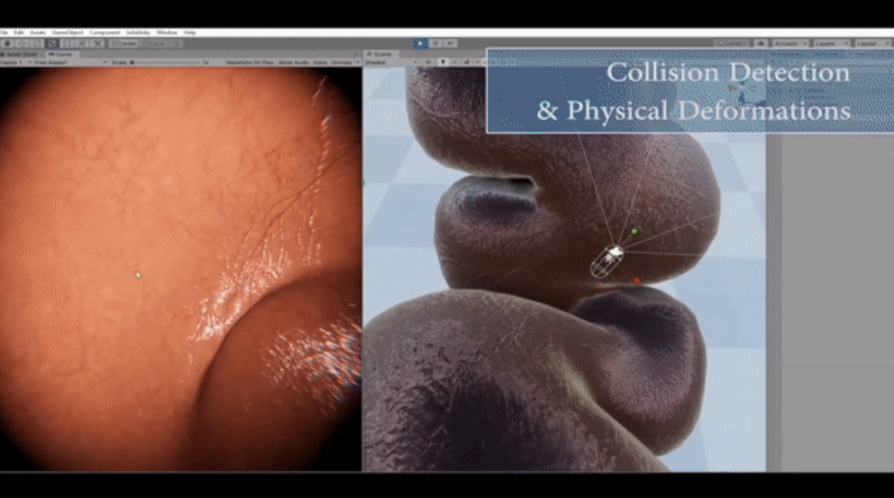

- DeepMIA (Deep Learning and Medical Image Analysis Laboratory)

https://deepmia.bogazici.edu.tr/

Areas of Study: He uses Deep Learning, image processing and computer vision techniques to solve problems in the field of artificial intelligence in health. She develops multi-modality artificial intelligence models by combining clinical data, histopathology and radiology images and genetic information of the patient.

Deep learning based tissue segmentation, Classification and grading in various cancer types and non-cancerous diseases, Artificial intelligence based survival analysis, Prediction of patients who develop treatment response, drug resistance or side effects, Synthetic image generation for histopathological staining and contrast radiology images, Detection of organ rejection after transplantation from biopsy images.

- Robotics Laboratory

https://bme.bogazici.edu.tr/robotics-laboratory